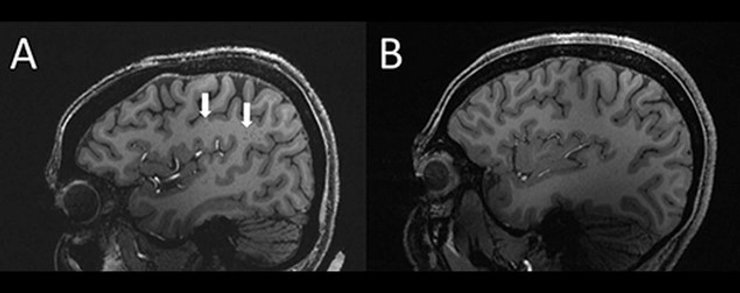

Стрелки показывают увеличенные периваскулярные пространства в головном мозге человека с хронической мигренью (слева) по сравнению с мозгом здорового человека (справа)

Результаты исследования показали, что периваскулярные пространства в мозге этих людей были значительно увеличены по сравнению с такими же пространствами в мозге здоровых добровольцев, которые были контрольной группой в исследовании.